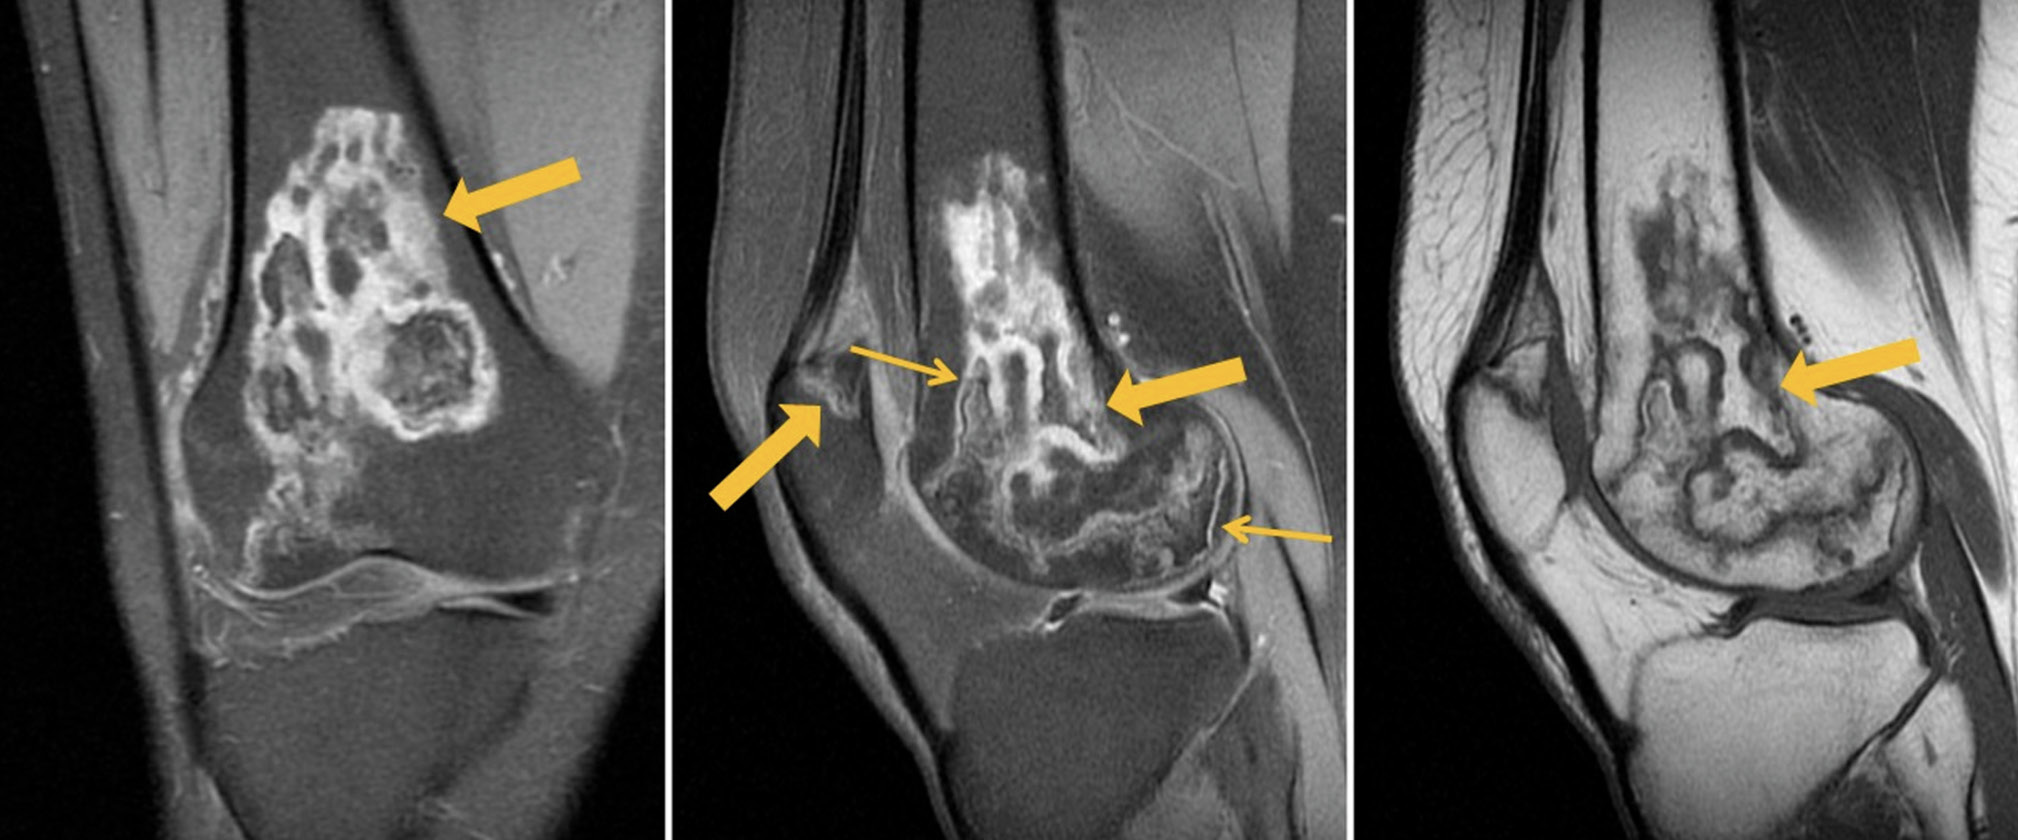

MRI of the left knee joint: lesions in the distal parts of the femoral diaphysis and femoral condyles (with involvement of the articular surface) as well as in the patella, inhomogeneously hyperintense on PD-weighted (proton-weighted) images with fat suppression and hypo-/isointense on T1-weighted images (T1WI), with an irregular (“geographic”) shape and yellow marrow signal areas visualized in the central parts (Fig. 1). MRI of the right knee joint: similar lesions of the bone marrow of both femoral condyles, with involvement of the distal metaepiphysis and articular surface of the lateral condyle as well as the patella. A perilesional “double line” sign is visualized over a short distance for some lesions (Fig. 2).

Fig. 1. Primary MRI of the left knee joint: PDWI with fat suppression in the coronal (а) and sagittal (b) plane and T1WI in the sagittal plane (с). The arrows indicate areas of bone marrow edema in the form of a heterogeneous, irregularly shaped (“geographic”) MRI signal of femoral and tibial condyles.